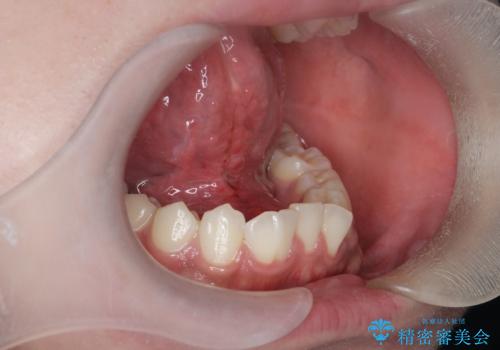

滑舌の改善 舌小帯の形成術

- 友人に滑舌の悪さを指摘され、改善を求めて来院されました。

舌下部に位置する小帯(ヒダ)の長い付着が認められるので、形成術を行うことで滑舌の改善を計画します。